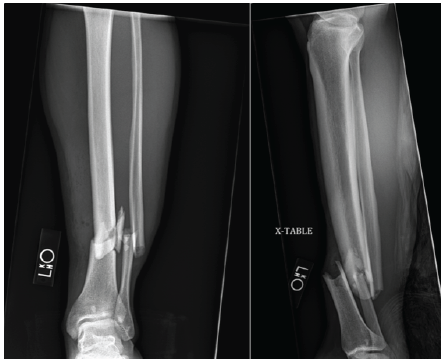

A 32-year-old non-smoking Caucasian male sustained a left grade one open tibia and fibula fracture following a motor vehicle accident. This can be seen in Fig. 1. Initial management included open reduction and internal fixation with an interlocked intramedullary nail and irrigation and debridement of the open fracture. The patient had no history of diabetes, smoking, or alcohol abuse. Family history was negative for osteoporosis or metabolic bone disease. He reported decreased libido and fatigue but had not undergone prior endocrine evaluation.

Figure 1: Radiographs of the left tibia and fibular fracture associated with a Gustilo-Anderson grade 1 open fracture with intact neurological and vascular status.